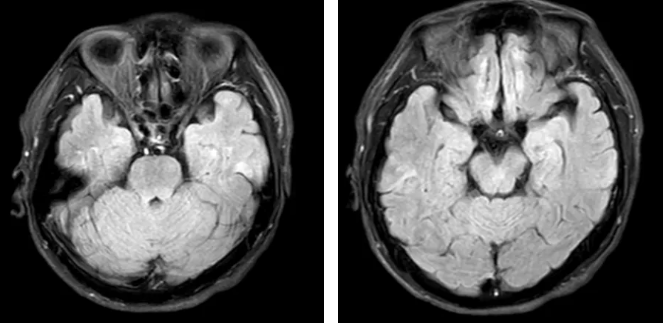

患者男性,56岁,既往无“高血压、糖尿病、冠心病、脑梗死”病史,近期有过度劳累史,此次发病表现为突发精神行为异常,言语混乱,情绪亢奋,偶有不明原因大哭,伴被害妄想,一般查体提示“口周疱疹”,神经系统查体可见行为失抑制,记忆力、计算力下降,入院后完善头颅核磁、脑电图、腰椎穿刺等一系列检验检查,最终确诊为单纯疱疹病毒性脑炎,治疗上给予“地塞米松磷酸钠注射液”减轻炎症减轻脑水肿、“注射用阿昔洛韦”抗病毒、“甲钴胺注射液”营养神经、“富马酸喹硫平片”抗精神症状、护胃、补钾、营养支持等综合治疗,患者的病情很快便得到了控制,经过10多天的精心治疗和护理,最终治愈出院。

患者头颅核磁提示双侧颞叶异常高信号

3.头颅核磁检查:显示正常或者以皮层为主的脑实质病变。